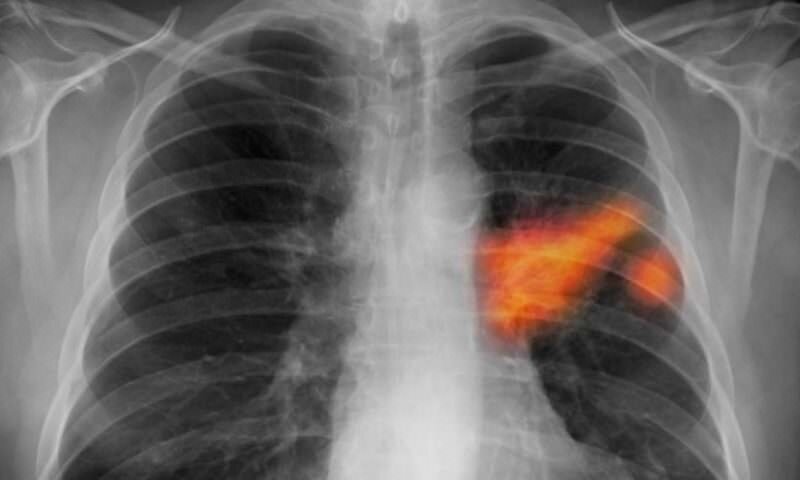

Рак легких на рентгеновских снимках

Рентген легких при онкологическом заболевании не всегда оказывается информативным, то есть способен демонстрировать затемнение или просветление. Кроме того, первая степень патологии также определяется далеко не всегда, за счет незначительных размеров новообразования до 5 мм. Несмотря на это, рентгенография является одним из самых достоверных методов диагностики рака на любой стадии. Для того чтобы результаты оказались максимально достоверными, рекомендуется осуществлять исследование не только в прямой, но и в боковой проекции.

Центральная форма рака легких на снимке

Идентификация центрального рака легких возможна по целому перечню, так называемых, рентгенологических симптомов. Речь идет о дестабилизации вентиляции, инфильтрации (выглядит на снимке, как темное пятно) и компенсаторной воздушности участков, находящихся поблизости. В целом, синдромы злокачественного формирования определяются как типичные, а потому постановка диагноза не вызывает затруднений.

При центральной форме рака четко идентифицируется начальное узловое формирование (имеет бугристый контур и неоднородное строение). Присутствуют изъязвления с какой-либо из сторон. Также следует учитывать, что инфильтрация легочных тканей без начальных узлов не должна восприниматься как отсутствие онкологии. При диагностировании центральной формы рака легких следует обратить внимание на то, что:

При центральном типе рака на рентгене видны такие изменения, как затемнение, отсутствие какой-либо разницы между границей кардии и диафрагмы. Помимо этого, идентифицируется изменение, связанное с положением диафрагмы и сердечной мышцы. Это касается начальной формы, в то время как на более поздних этапах не заметить значительный по своим размерам опухолевый узел просто невозможно.

Затемненный узел может характеризоваться различной величиной и формой. В случае расположения пятнышка на периферии, ему характерна овальная форма. В некоторых ситуациях тень узла с непропорциональной формой может располагаться вблизи от средостения. О том, что рентген легких в этом случае точно определил злокачественное новообразование легких, свидетельствуют некоторые признаки: